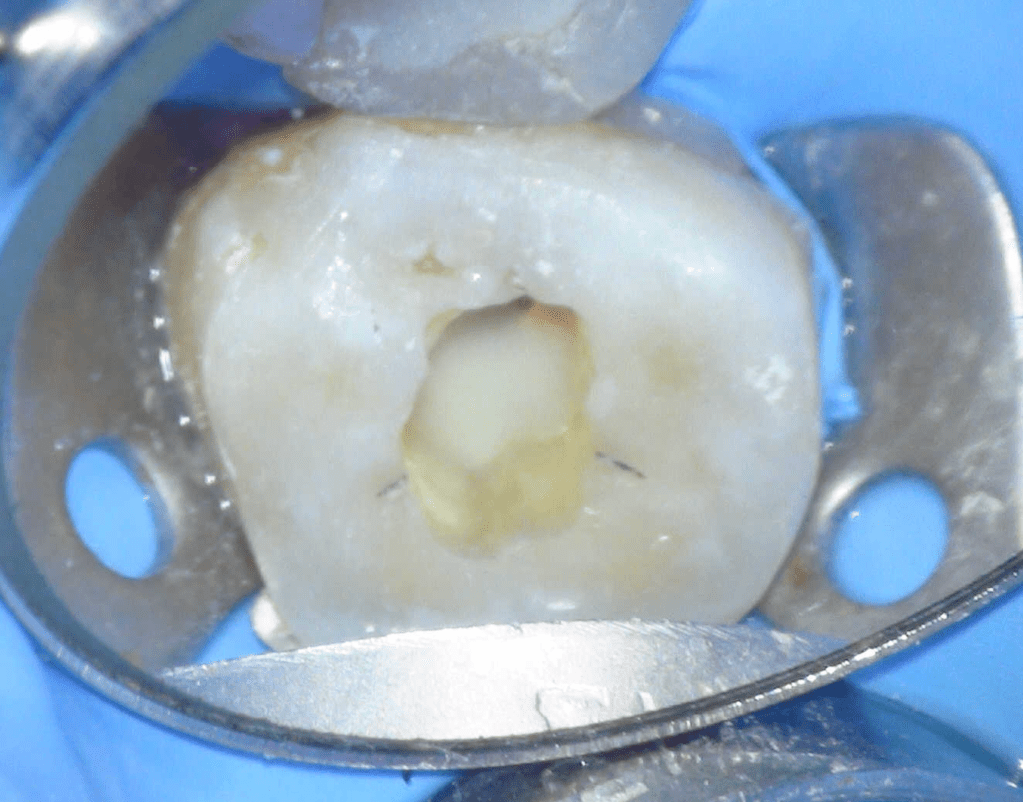

Pulpotomía biodentine + reco preendio